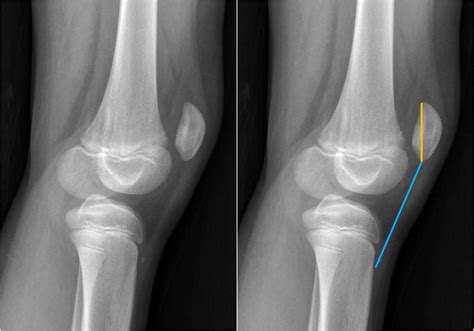

• Imaging Tests: X-rays, MRI, or CT scans to visualize the patella and surrounding structures. These tests can help identify any anatomical abnormalities or soft tissue injuries.